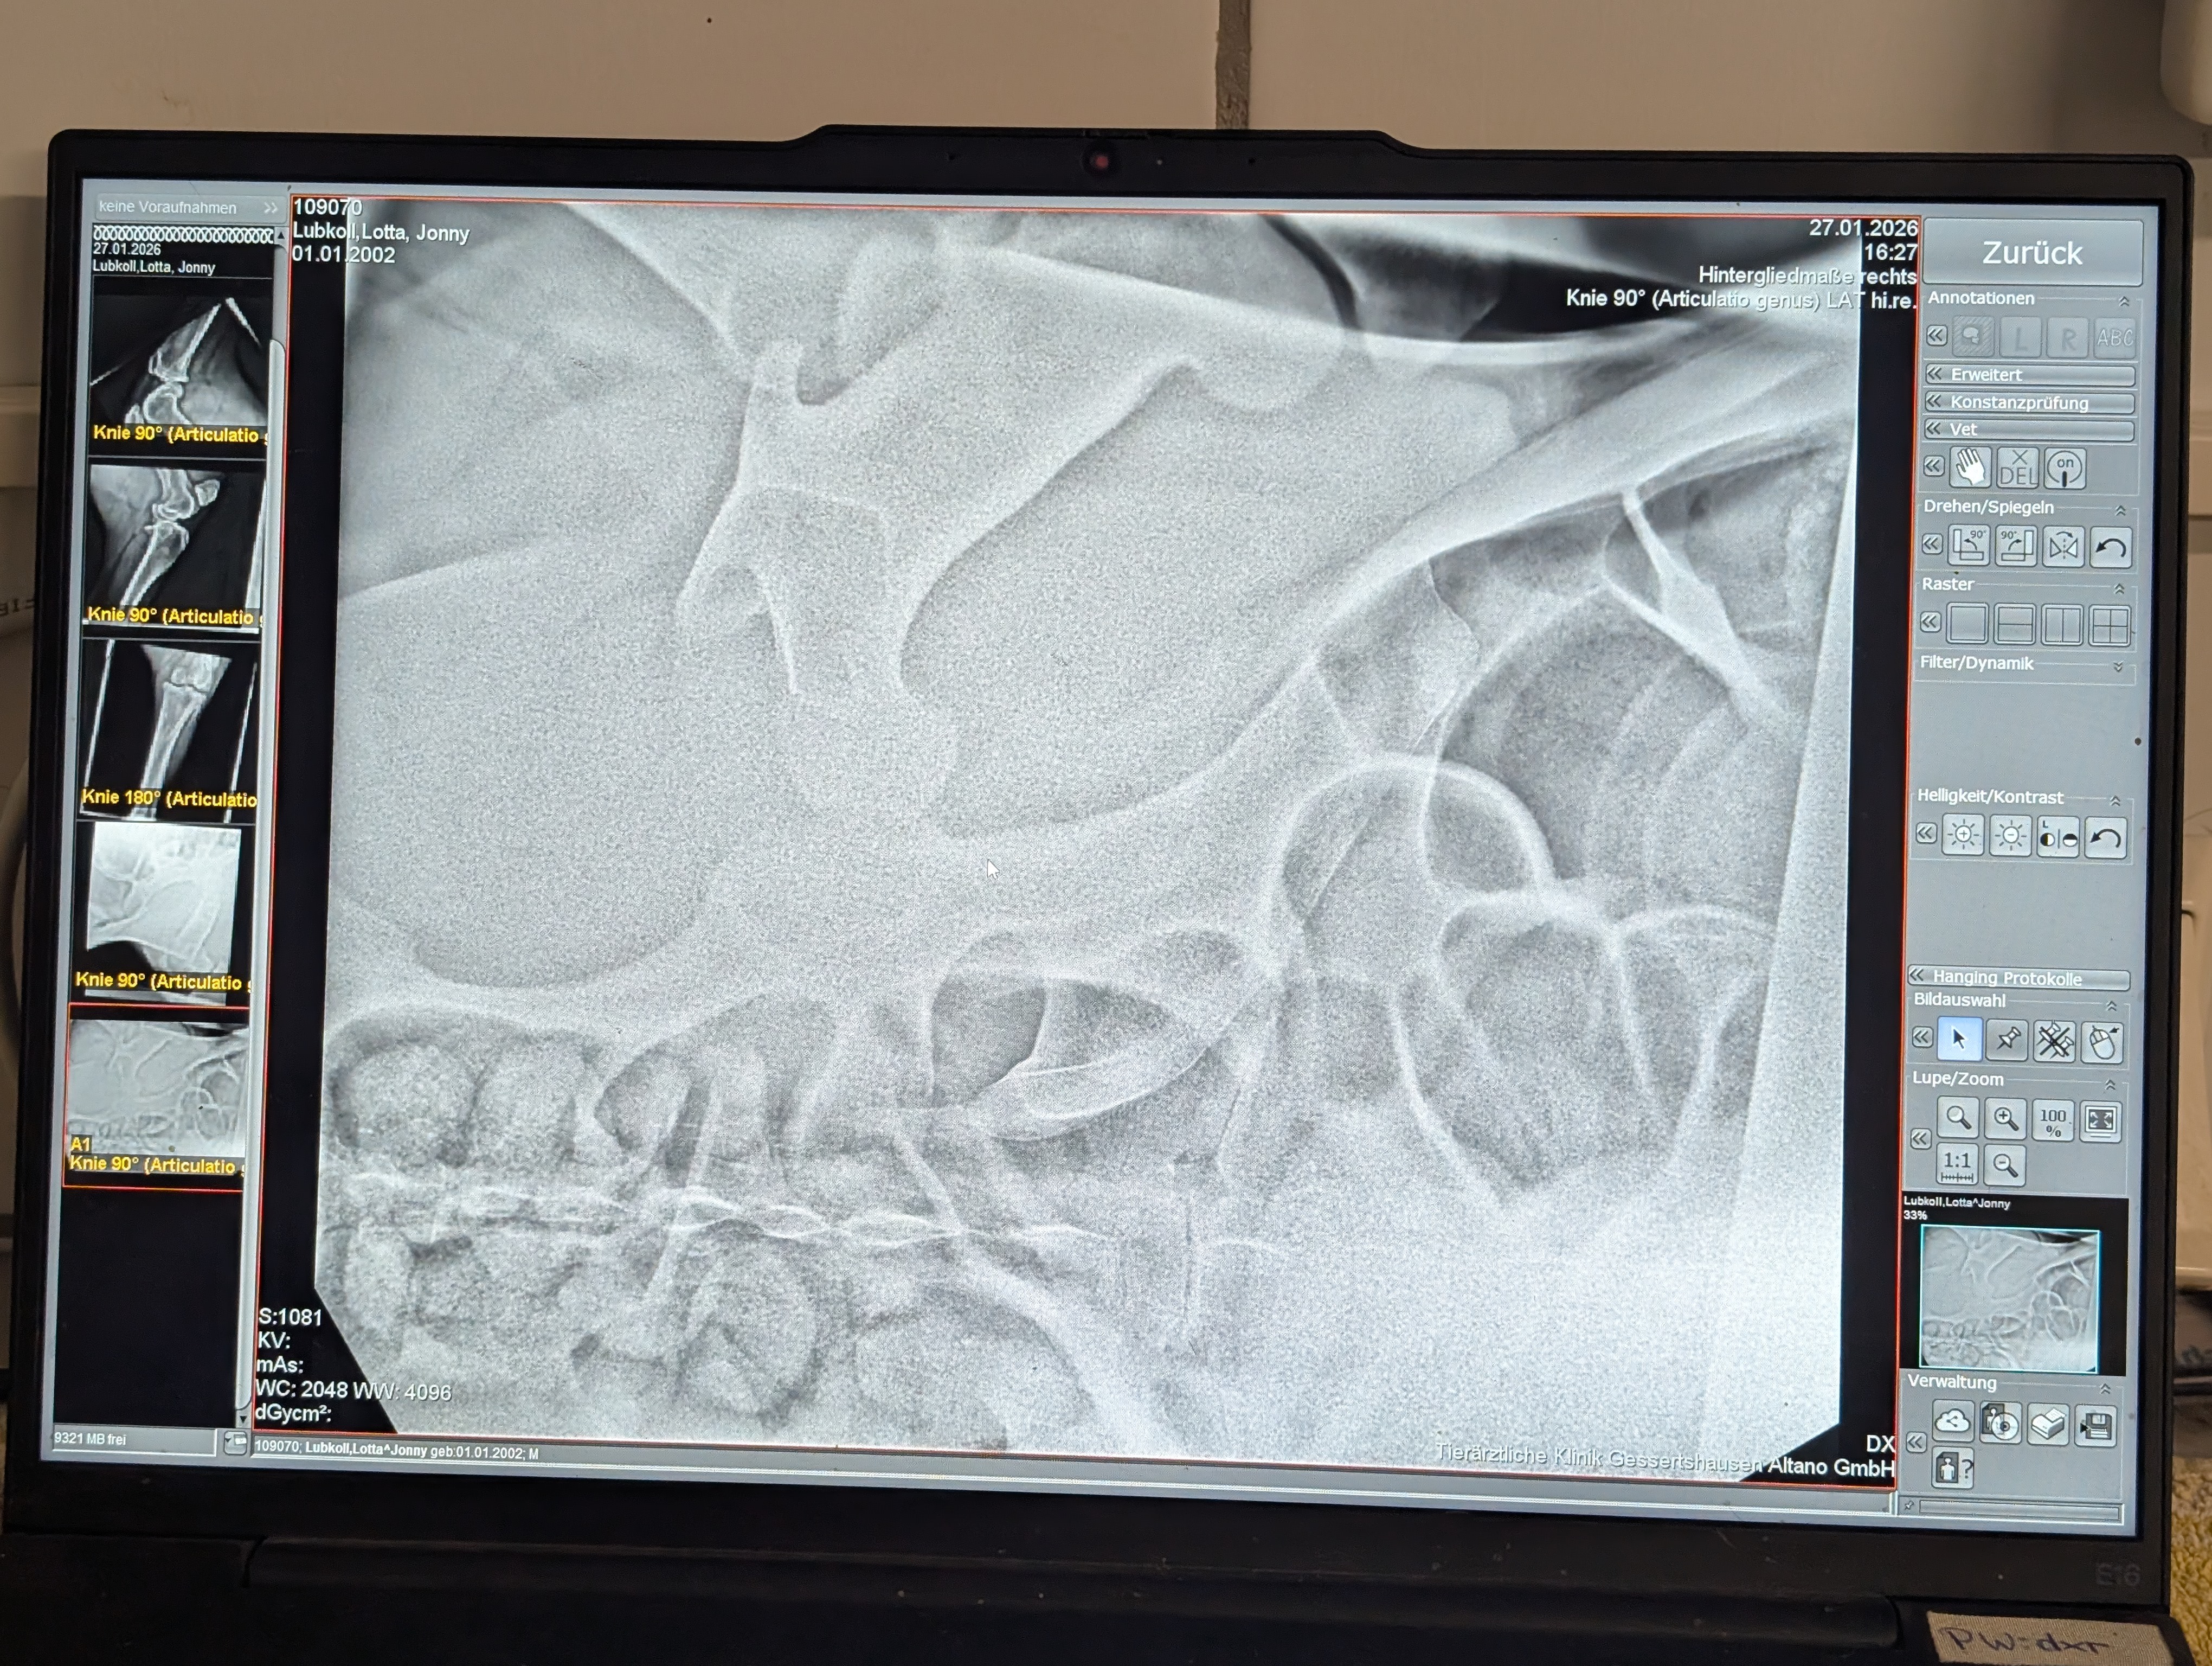

Durch die eisige Wetterlage ist er ausgerutscht und hat sich dabei das Hüftgelenk luxiert. Jetzt steht er in der Tierklinik Gessertshausen. Er frisst, er hat Lebensmut.

Die medizinische Versorgung und Nachsorge ist aufwendig und mit hohen Kosten verbunden. OP, CT, Röntgen, mindestens zwei Wochen Klinikaufenthalt, Nachsorge..